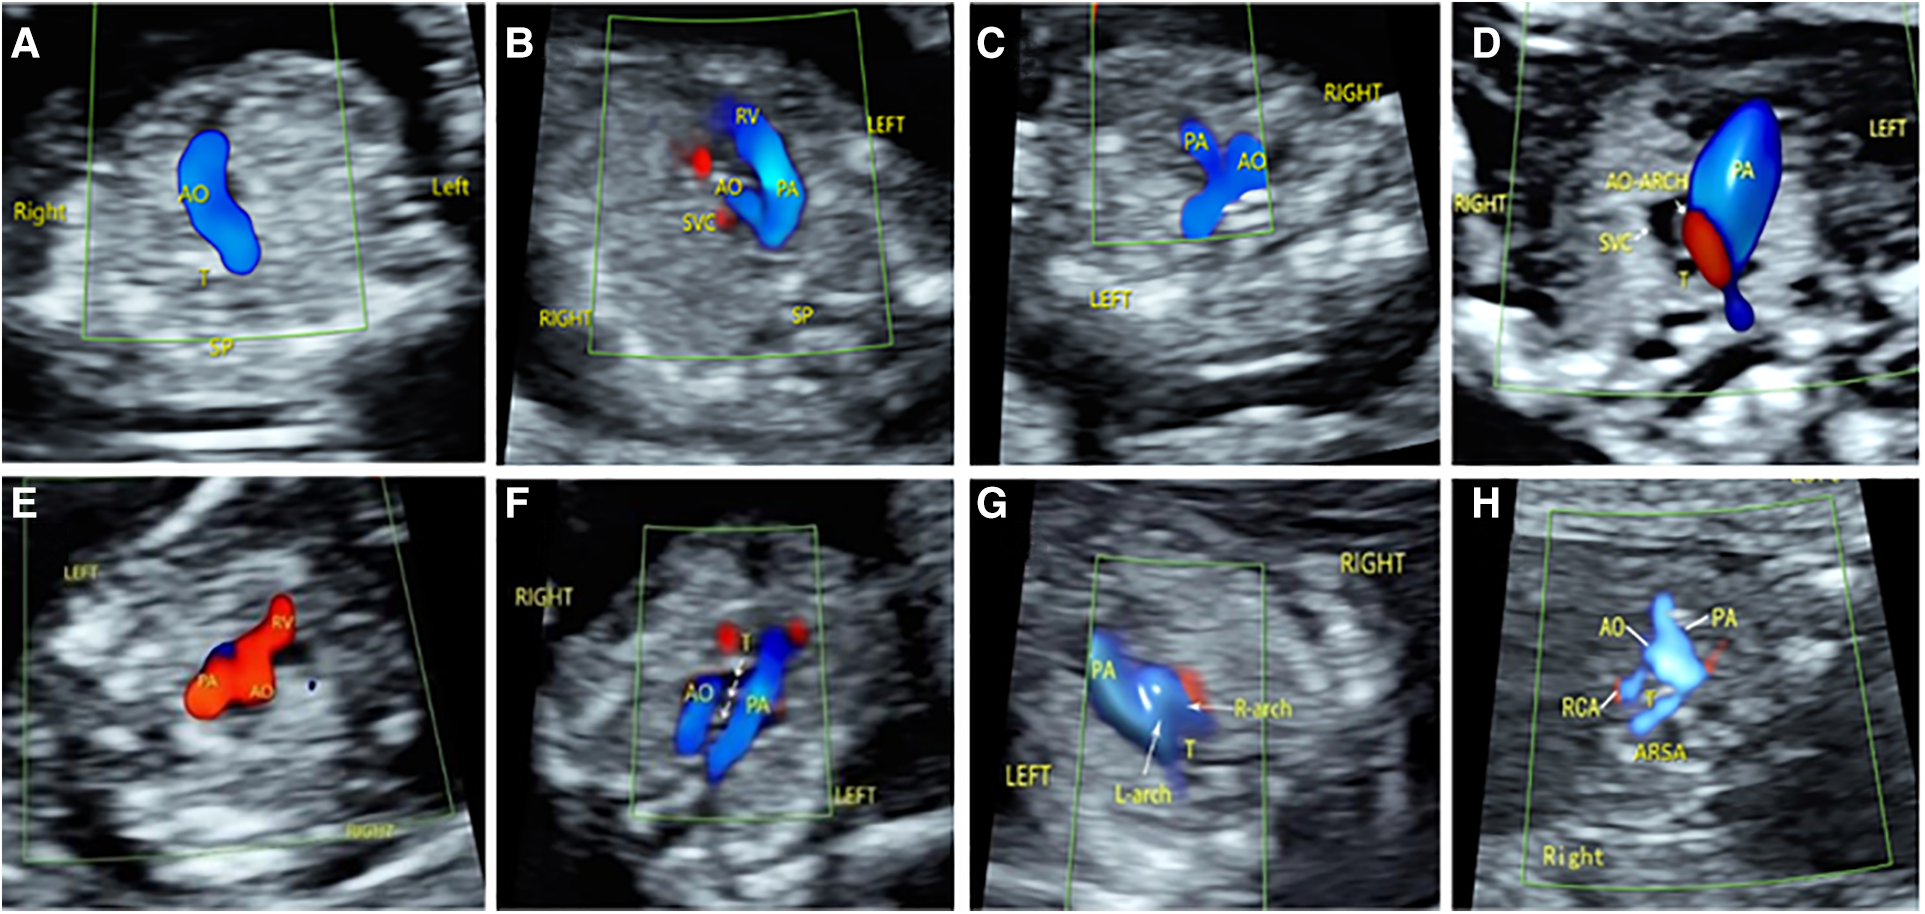

Among the 176 fetuses with CHD, 10 fetuses had an abnormal upper abdominal transverse section. According to the integrity of the fetal abdominal wall and the spatial position of four U-shaped structures (gastric bleb, inferior vena cava, aorta, and spine), four abnormal image patterns of UAb transverse section were found, which could be seen in normal cases, situs inversus, left isomerism syndrome, and right isomerism syndrome (Figure 4). According to the location, size, cardiac axis, the central crisscross structure of the heart and the size and direction of blood flow bundles, 16 kinds of 4CV section abnormal patterns were found (Figure 5). According to the number of large arteries, the relationship between the pulmonary artery and the aorta, the diameter of the pulmonary artery and the aorta, and the direction of blood flow between the ductus arteriosus and the aortic arch, eight abnormal patterns of 3VT section were found (Figure 6). According to the course of bilateral subclavian arteries, two abnormal patterns of BSa sections were found (Figure 7).

Figure 6

Abnormal ultrasound image pattern of 3VT section. (A) Patterns of 3VT-1, one vessel with a curved course or a straight course. (B) Patterns of 3VT-2: The aorta was smaller than the pulmonary artery. (C) Patterns of 3VT-3: The pulmonary artery was smaller than the aorta. (D) The aorta was smaller than the pulmonary artery, and reverse flow was observed in the aortic arch. (E) The “in–out sign” of the aorta and/or pulmonary artery. (F) Patterns of 3VT-6, two large arteries forming a “U” sign around the trachea. (G) Patterns of 3VT-7, two large arteries forming an “O” sign around the trachea. (G) Patterns of 3VT-8: The subclavian artery and aorta together form a “C” sign around the trachea. (H) Patterns of 3VT-8: The subclavian artery originates from the origin of the descending aorta and runs behind the trachea to form a “C”-type vascular ring.

Figure 7

Abnormal ultrasound image pattern of the bilateral subclavian artery section. (A) Normal bilateral subclavian arteries are in front of the trachea, and they form a “bow” structure. (B) BSa-1 pattern: The right subclavian artery originates from the descending aorta, bypasses the trachea, and then runs to the right. (C) BSa-2 pattern shows that the left subclavian artery originates from the descending aorta and is circumvented behind the trachea to the left.

In this study, 3VT section abnormalities were most seen in outflow tract malformations. The abnormal image patterns can be divided into eight categories. The single arterial blood flow bundle can be divided into two types according to its course (24). The single arterial blood flow bundle is vertically oriented, suggesting a pulmonary bundle, which is common in HLHS; if the single arterial blood flow bundle is curved to the side, it suggests an aortic arch blood flow bundle, which is common in conotruncal defects. When a single blood flow bundle is found, the diagnosis should be further refined by observing the blood flow of the ductus arteriosus and the connection between the large artery and the ventricle. The proportion of blood flow bundles can also be divided into two types. A small aortic blood flow bundle, especially in 4CV views with right heart–dominant flow, suggests a narrowing of the aortic arch. Conversely, a narrow pulmonary artery blood flow bundle that forms a “Y” blood flow bundle with a widened aorta may indicate pulmonary stenosis, and it is most common in tetralogy of Fallot and can also be seen in type IV double outlet right ventricle and simple pulmonary artery stenosis (11). In atypical cases, ventricular septal defect and MPA/AO ratio can be suggested, and the diagnosis can be improved in the follow-up review (25). “Back and forth” flow bundles are characteristic of the absence of a semilunar valve, which can be seen in the absence of aortic valve, pulmonary valve, or bisemilunar valve. Some scholars call it “in and out” (26, 27). “U”-, “0”-, and “C”-shaped blood flow bundles are found in vascular rings formed by the abnormal aortic arch and its branches. It is difficult to accurately identify them in early pregnancy. To summarize, after obtaining a 3VT section under optimal conditions, if a “V” sign is not observed on this view, which is not formed by the ductus and aortic arch, careful analysis of the abnormal pattern is needed, and multiple sections should further confirm the diagnosis. The bilateral subclavian artery section is an effective complement to 3VT section. Because the angle between the acoustic beam and the flow direction of the right subclavian artery is too large, it is difficult to show the aberrant subclavian artery on the 3VT section. In contrast, the transverse “arch,” like the structure of the bilateral subclavian artery, is easy to identify. By observing the spatial location of bilateral subclavian arteries and their relationship with the trachea, their abnormal image patterns can be divided into two categories. Failure to show this typical structure suggests the presence of an aberrant subclavian artery.